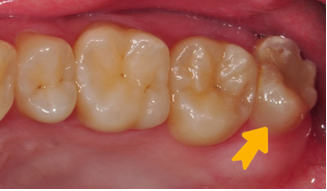

等待傷口恢復(約三個月)3.拆除固定鐵線、並將牙齒修型

4.裝上假牙,完成治療